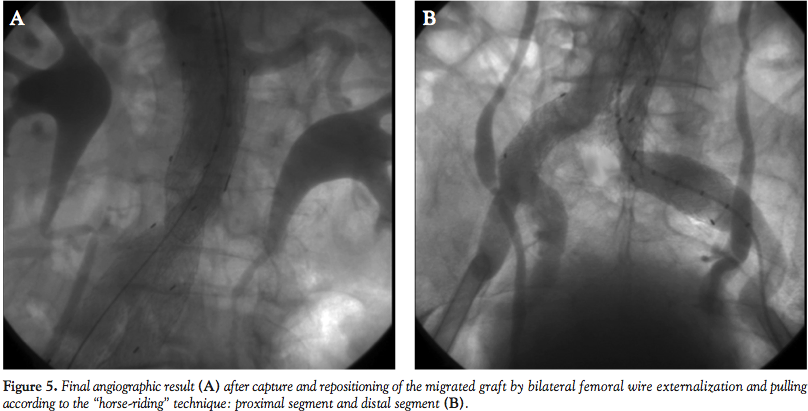

The procedure was then completed by deploying a 20 x 14 cm contralateral leg during inflation of a 34 mm tri-lobated balloon (W. L. Gore) in the EVG body at the level of the proximal stent edge, to stabilize the graft during contralateral sheet gate insertion, with a satisfactory final result (Figure 5). The patient was discharged two days after the procedure, and blood draws did not disclose any evidence of renal damage. Computed tomography demonstrated complete AAA exclusion without any endoleak at up to 6 months follow-up.